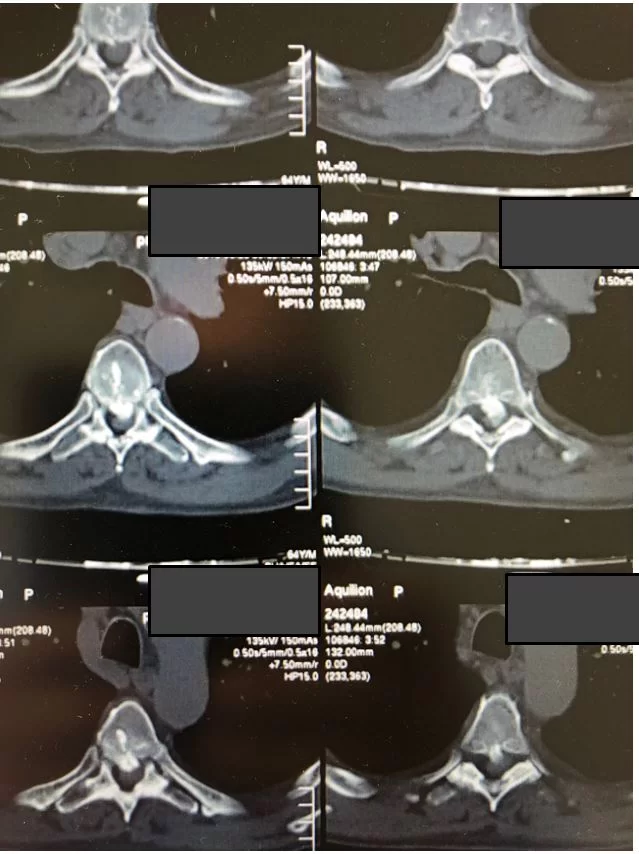

Ο απεικονιστικός έλεγχος ανέδειξε δύο επασβεστωμένες θωρακικές δισκοκήλες στο ύψος Θ6/7 και Θ7/8.

Οι θωρακικές δισκοκήλες, ειδικά όταν είναι επασβεστωμένες, αποτελούν χειρουργική πρόκληση, μια και η δισκοκήλη είναι σε άμεση επαφή με το νωτιαίο μυελό, ενώ στην προσπέλαση είναι σημαντικό να διαφυλαχθούν σημαντικές δομές όπως τα μεγάλα αγγεία του θώρακα, ο πνέυμονας κλπ.